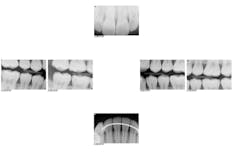

For example, 18-year-old twins presented to my office recently. The referring practice was not able to supply clinically readable digital x-rays. To get the twins comfortable and start the diagnostic process, I used CariVu. I was able to determine that they did not have occlusal or interproximal caries, and consequently, they had no need for treatment at the time (figures 2 and 3). These young men remarked, "Dr. McKibben has all of the latest technology." They will probably even tell their friends and family. Although I am an older practitioner, I still want to maintain a reputation of being on the cutting edge of innovation. CariVu, along with my other technologies such as CAD/CAM, helps with that perception.

Figure 2: One of the twins' CariVu images that shows no caries. Note the lighter enamel border around the darker dentin.

Figure 3: Image of interproximal caries from another patient. Caries is more porous, so appears darker.